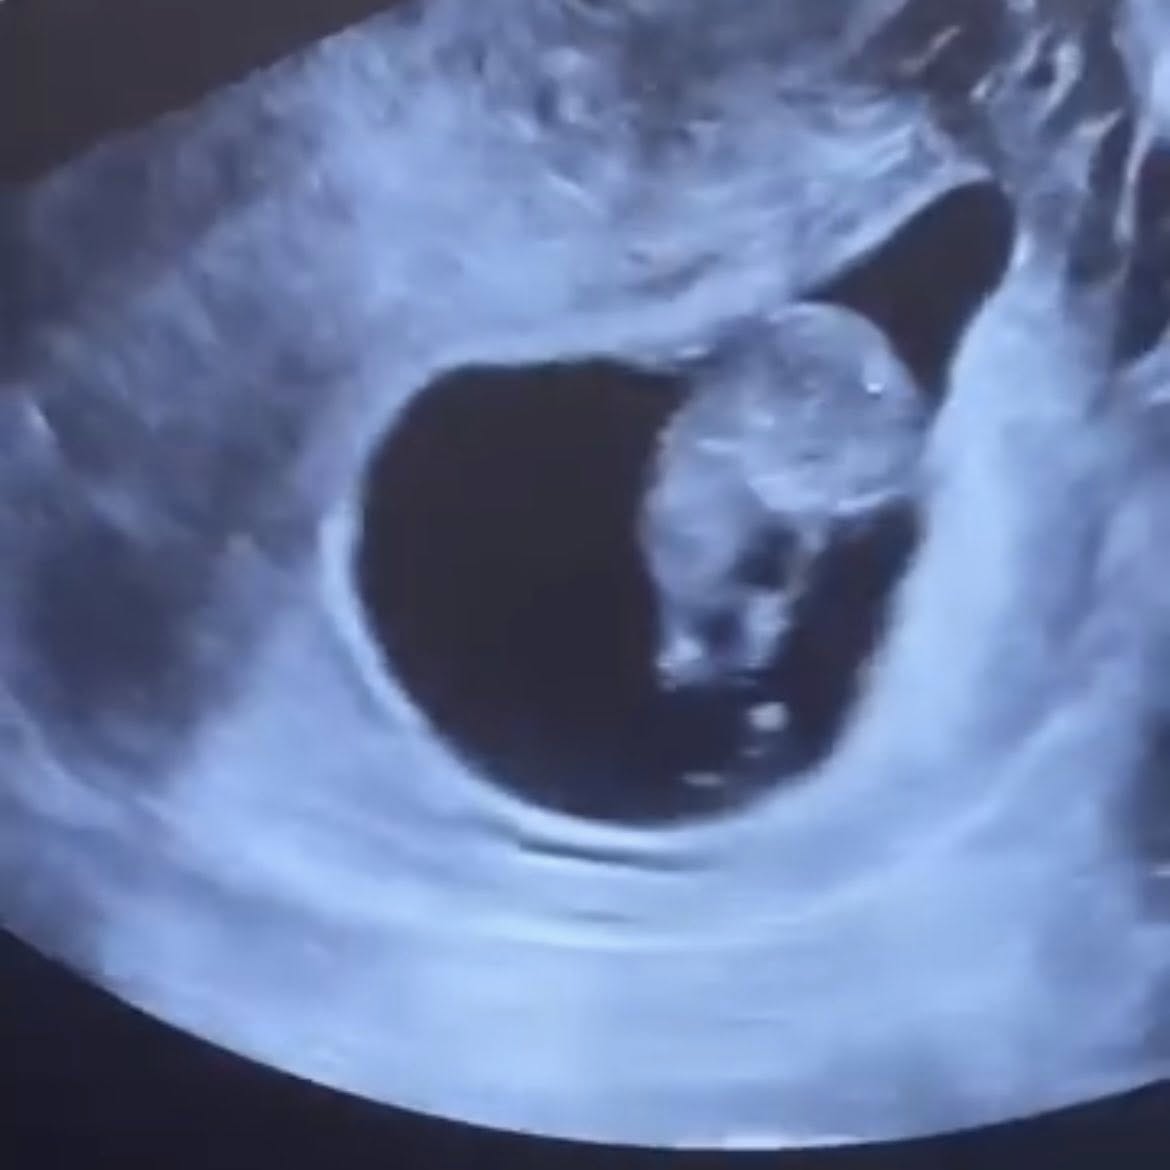

กว่า 6 ปีของความหวัง ความพยายาม และการเฝ้ารอ “นุ่น รมิดา” และ “หลุยส์ สก๊อต” เดินผ่านวันที่ยากที่สุดของคำว่า “อยากมีลูก” ผ่านความสูญเสีย ผ่านความเจ็บปวดจากการแท้ง จนในที่สุด ปาฏิหาริย์ก็เหมือนจะเกิดขึ้นอีกครั้ง